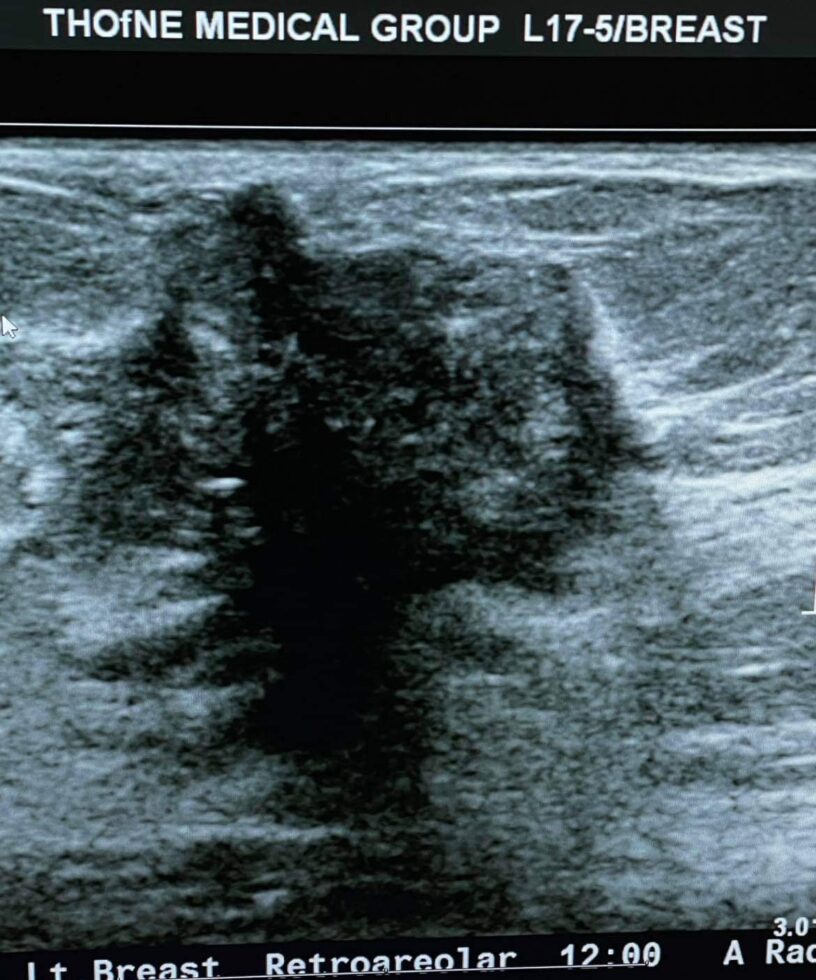

Tu cijelu godinu grudi su me jako svrbjele. Lijeva bradavica u dojke se povlačila unutra a ja sam sve to ignorisala. Pominjala sam sestri, mami, pa čak i mužu. Napokon, krajem decembra 2021. godine, mama se na mene doslovno izgalamila s onim našim “ ko će te čuvati ako nećeš samu sebe” i pod pritiskom zakazala sam termin. Čim sam otišla kod ginekologa sutradan, dalje me je poslala u bolnicu na pregled, a nakon toga i na biopsiju.

Tu cijelu godinu grudi su me jako svrbjele. Lijeva bradavica u dojke se povlačila unutra a ja sam sve to ignorisala. Pominjala sam sestri, mami, pa čak i mužu. Napokon, krajem decembra 2021. godine, mama se na mene doslovno izgalamila s onim našim “ ko će te čuvati ako nećeš samu sebe” i pod pritiskom zakazala sam termin. Čim sam otišla kod ginekologa sutradan, dalje me je poslala u bolnicu na pregled, a nakon toga i na biopsiju.

Ja imam rak dojke, lijeve, i imam rak limfni čvorova isto na lijevoj strani.

Doktorica mi je odmah rekla da mi neće moći spasiti bradavicu i naravno da će mi grudi ostati poprilično unakažene i da ih mora odstraniti gotovo 90%. Druga operacija je uklanjanje limfnog čvora gdje je rak, ispod pazuha. Nije me to uopšte potreslo, jer su to samo riječi, ali onaj dan kada sam vidjela stotine slike kod plastičnog hirurga drugih žena kojima se isto desilo, htjela sam vrištati. Samo sam šutjela i mahala glavom na sve što je govorio, a nemam pojma ni šta mi je rekao. Stotine slika mi je pokazao kako će to sve izgledati poslije operacije kad se ukloni rak. Znači prije radijacije i hemoterapije. Užas! Nisam plakala ali sam se upitala – zar se ovo stvarno dešava ili sam ja u nekoj noćnoj mori? Brzo sam se probudila dok je doktor trabunjao o proceduri o kojoj nisam zapamtila možda dvije riječi. Jedino znam da sam na kraju izašla iz kancelarije mrtva-hladna, totalno utrnula. Nisam uopće razmišljala više o hirurgu i brzo sam taj dan odlučila da ne želim rekonstrukciju grudi nego da mi se zaliječi rana pa tek onda nakon godinu ili kad već zarastu rane, tada ću pokrenuti te ostale rekonstruktivne procedure. Za sada prvenstveno želim da uklone rak s operacijom, radijacijom i hemoterapijom. Rekonstrukcija je meni lično kozmetička popravka koja je i nebitna, jer na kraju krajeva, ja se osjećam svakako sakata i to će tako biti do kraja mog života. Ovo go**o u meni vlada mojim tijelom, a ja ništa nemogu da poduzmem, ama bas ništa.